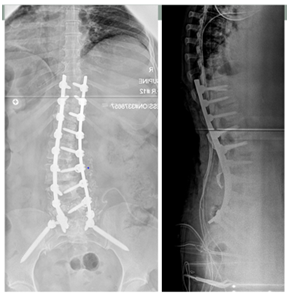

- Anterior column reconstruction with cages especially at Lumbo- sacral junction is necessary and always required to restore sagittal balance (Figure 3).

- These techniques became more frequently required for balance restoration in rigid and severely rigid curves of the thoracic and lumbar spine.1 (Figure 4a & 4b).

Figure 4a Smith Petersen Osteotomy.

Figure 4b Three Column Pedicle Subtraction Osteotomy.

Smith Petersen Osteotomy |

Three Column Pedicle Subtraction Osteotomy |

For the patient requiring 10° to 20° of lordosis or 4 to 7 cm of correction of the C7 plum line. |

For the patient requiring 20° to 35° of lordosis or 10 cm of correction of the C7 plum line. |

Needs a mobile disc. |

_ |

The osteotomy hinges on the posterior aspect of the disk |

The osteotomy hinges on the anterior cortex |

Lengthens Ant Column. |

Shortens post Column. |

Table 1 Differences between SPO vs PSO.

Figure 7 Spino pelvic alignment after surgical correction for developmental spondylolisthesis.